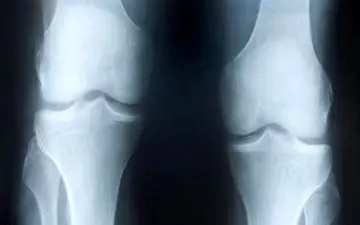

آرتروز زانو بیماری شایعی است که احتمالا خودتان یا یکی دو نفر از بستگان میانسال شما هم به آن مبتلا هستند.بیمارانی که…

جراح زانو با اشاره به شیوع بالای آرتروز زانو در جامعه روش هایی را برای جلوگیری از این عارضه استخوانی تشریح کرد.

دبیر برنامه ارتوپدی در کنگره جامعه جراحان ایران با اشاره به اینکه ساییدگی زانو از بین آرتروز های کل بدن شایع تر است،…